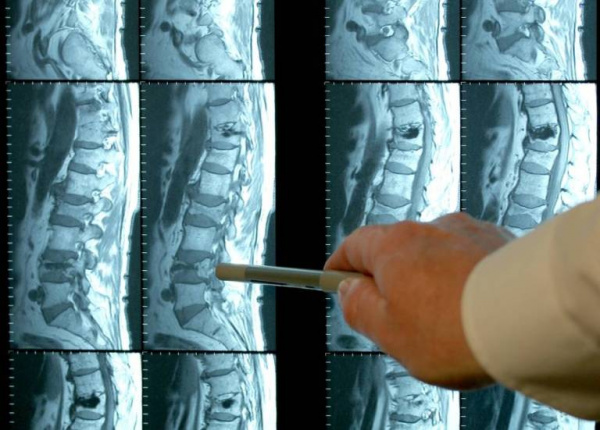

- МРТ позвоночника. Определяется снижение интенсивности сигнала на Т1-взвешенных снимках и его повышение на Т2-взвешенных изображениях, деформация межпозвоночных дисков, структурные изменения тел позвонков. Чувствительность магнитно-резонансной томографии достигает 96%, точность – 94%, поэтому ее считают «золотым стандартом» диагностики.

2. Современная диагностика спондилодисцитов: основные КТ- и МРТ-признаки/ А.С. Винокуров, О.И. Беленькая, А.Л. Юдин, А.В. Ким// Лучевая диагностика и терапия. – 2019. – №10.